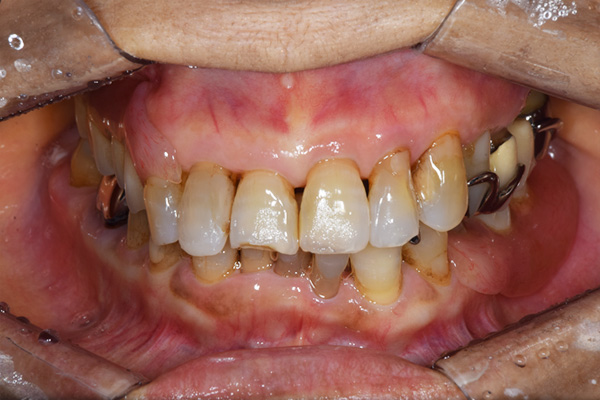

ケース1(自費の部分入れ歯)

前歯が折れて当院にいらっしゃいました。 過去に下の入れ歯を作ったが、合わなくなってずっと入れ歯をいれていらっしゃらない患者様でした。 これは奥歯で噛むことができないため、前歯で噛むことを繰り返したために、負担に耐えられなくなった前歯が折れてかぶせ物ごと 外れてしまったのだと考えられます。 痛くない、違和感の少ない、下の入れ歯を作ることがこの方のゴールであると考えられました。

入れ歯をお口の中にいれた状態です。前歯もMTMといって、歯を少し引っ張り出す処置を行なったことで、しっかり残せて、またかぶせ物をしました。